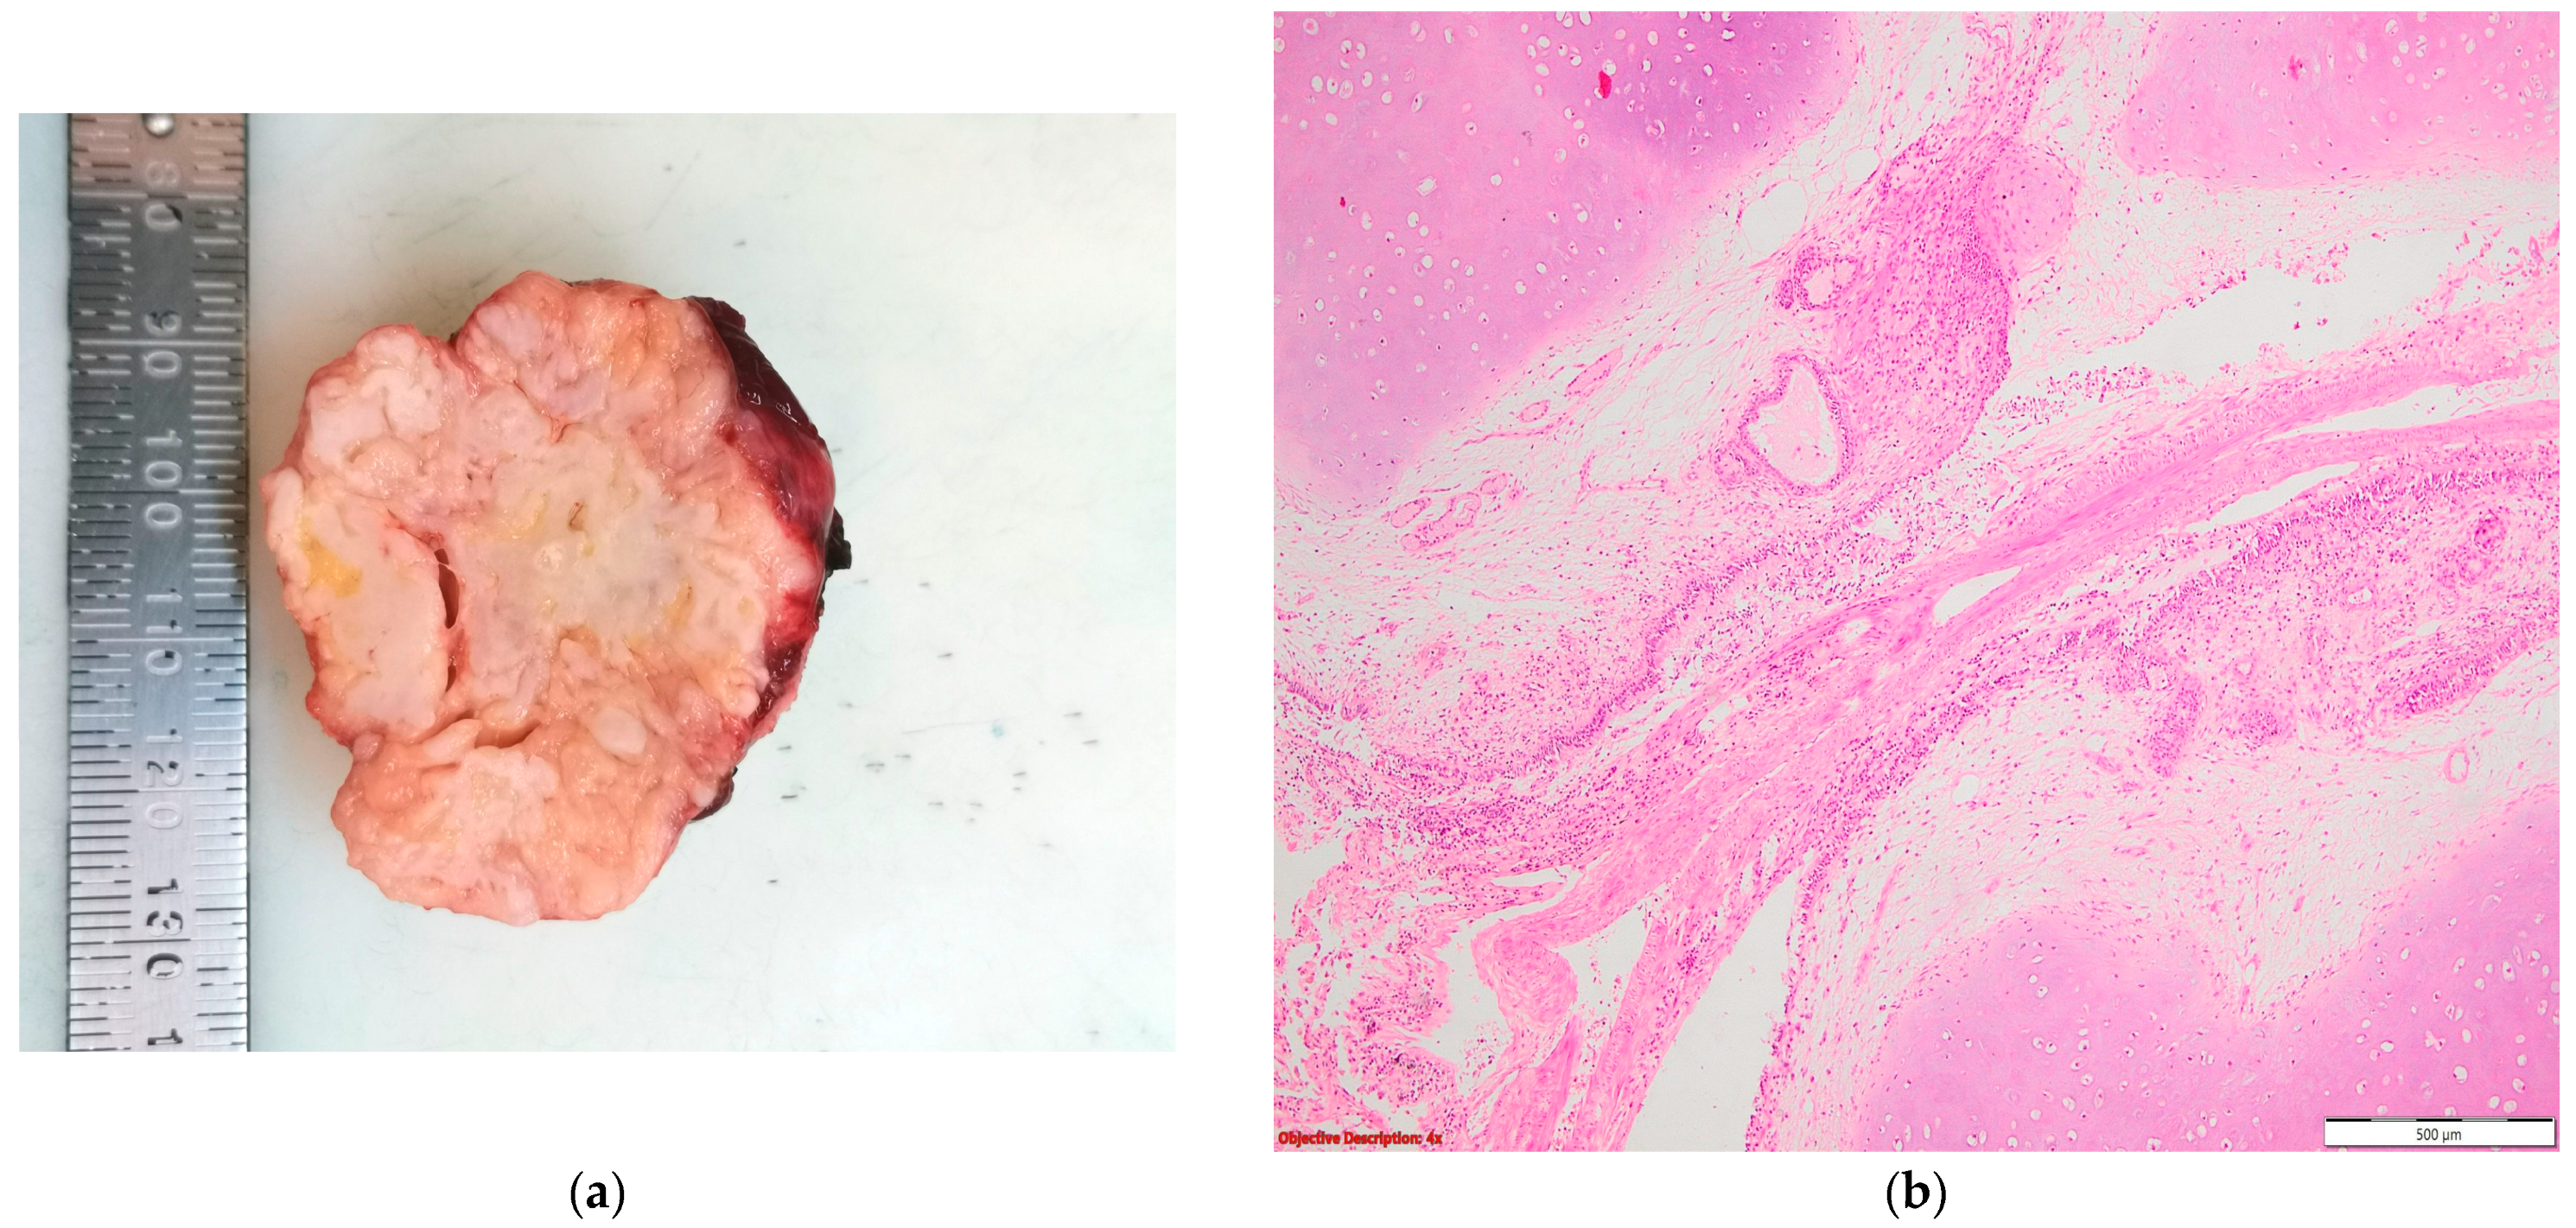

Figure 2.

Tuberculosis: (a) gross examination (fibronecrotic lesion—caseous necrosis); (b) microscopic examination (necrotizing granuloma including Langhans giant cells and epithelioid histiocytes; HE, 400×); and (c) microscopic examination (BAAR; Ziehl Neelsen, 1000×).

In the nine cases of NSCLC associated with granulomatous lesions, five of them were represented by active tuberculosis (Figure 2) and four by sarcoidosis (Figure 3).

Regarding the high prevalence of Mycobacterium tuberculosis in our country [2,7], all or part of the fibronodular lesions of the lung parenchyma (Figure 4), nodular calcification, and osseous/osteomedullary metaplasia (Figure 5) could represent sequelae of tuberculosis.